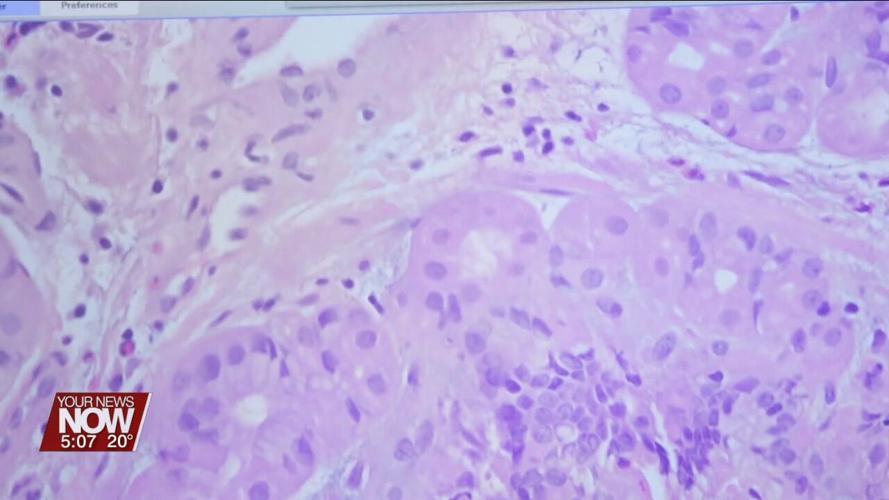

After weighing the options, surgery was the best route for Dennis. New technology in use at the Ohio State University Comprehensive Cancer Center—James Cancer Hospital and Solove Research Institute helps pathologists provide insights about the unique traits of each patient's cancer by converting biopsies into digital images that can be examined in microscopic detail from anywhere in the world.

"Once the slide is digitized, we can apply deep learning and artificial intelligence on these images to find really, really complicated answers," said Anil Parwani, MD, PhD at The Ohio State University Comprehensive Cancer Center.

The technology is being tested at the James in prostate, breast, gastric, and other cancer cases and continues to improve the longer it's used, banking outcomes from every new case and using artificial intelligence to predict how quickly a patient's cancer is likely to spread – a concept known as "Risk stratification."

Computerized screening extends beyond human eye Pathologists are trained to look at specific features of the cell that are seen through a microscope. Digital pathology took these cellular images – which are traditionally viewed on a series of single flat images on glass slides – and combined them into a single 3D image that can be studied from all angles on a computer. AI can find concerning features outside the cancer cell that are not obvious to the human eye. Parwani explains, these serve as signals to create a risk ranking (low to high) and give important information for guiding treatment decisions.